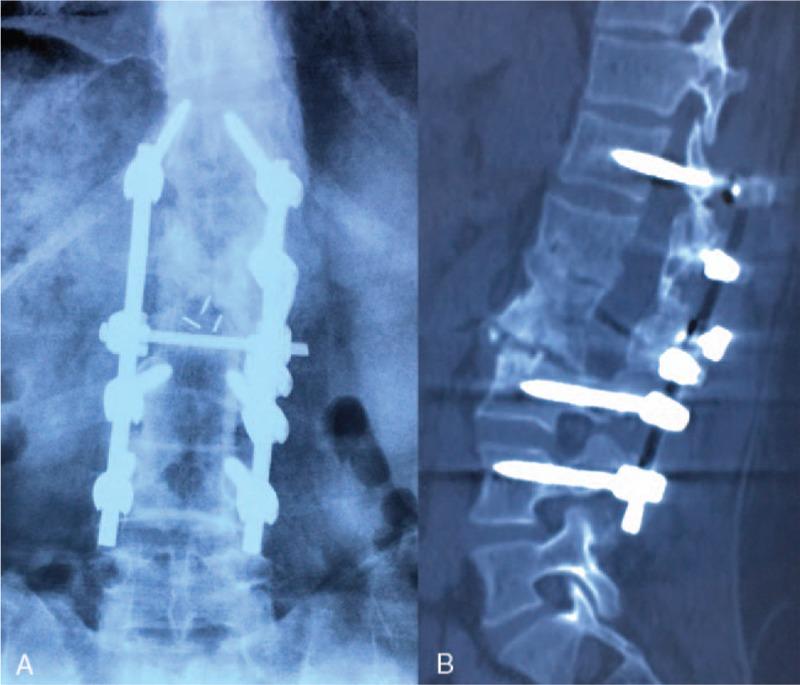

The patient underwent posterior reduction, combined intervertebral-posterolateral fusion, and internal fixation with screws and rods.

The patient was satisfied with the back pain relief after surgery and able to live a normal life at follow-up. The imageology showed a good correction of the deformity with a solid bony fusion.

患者接受了后路复位、椎间后外侧联合融合以及螺钉和棒内固定。

患者对术后背痛缓解情况满意,随访时能够正常生活。影像学检查显示畸形得到良好矫正,有稳固的骨融合。